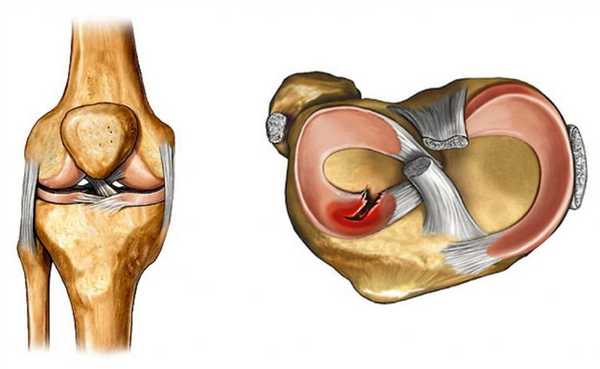

Для удобства диагностики и выбора оптимального лечения все повреждения медиального мениска колена разделяются на несколько основных групп в зависимости от нескольких критериев. По локализации выделяется изолированный разрыв заднего рога (встречается чаще всего), или тела мениска. В зависимости от выраженности нарушения целостности хрящевой ткани классификация включает:

Виды

- Частичный разрыв, при котором имеет место очаговое нарушение целостности с сохранением общей анатомической структуры и формы мениска.

- Полный разрыв – нарушение целостности затрагивает всю толщину хряща, при этом образуется отломок, который может смещаться относительно других структур колена.

Для более точного определения выраженности повреждения существует классификация по Stoller, в которой выделяется 4 степени:

- 0 степень – изменений нет.

- 1 степени – имеются небольшие очаговые изменения.

- 2 степень – более выраженные изменения, имеющие линейную форму и не выходящие за поверхность хряща.

- 3 степень – изменения затрагивают всю толщу хряща, при этом имеет место полный разрыв мениска.

Классификация разрыва внутреннего мениска колена возможна на основании результатов тщательного клинического обследования, а также данных объективной диагностики, в частности с использованием МРТ (магнитно-резонансная томография необходима для классификации по Stoller).

Нарушение структуры и формы медиального мениска в области заднего рога классифицируется по нескольким критериям. В зависимости от выраженности травмы выделяется:

степени повреждения мениска

В зависимости от основного причинного фактора, приведшего к развитию патологического состояния хрящевых структур колена, выделяется травматическое и патологическое дегенеративное повреждение заднего рога медиального мениска.

По критерию давности перенесенной травмы или патологического нарушения целостности данной хрящевой структуры выделяется свежее и застарелое повреждение заднего рога медиального мениска. Также отдельно выделено комбинированное повреждение тела и заднего рога медиального мениска.